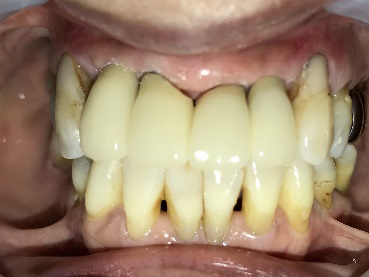

男性Kさん 50代(インプラント)

主訴

歯がグラグラするところ、むし歯のところ、しみるところ、被せ物がとれたところ、歯茎が腫れて血が出るところ、歯が抜けているところがある。すべて治したい。

治療内容

残っている歯を抜歯し、上下インプラント治療をしました。

所感

歯周病が進行している歯、むし歯が進行している歯がほとんどで、レントゲンを撮り、詳しく診てみると、ほとんどの歯を保存することができないことがわかりました。抜歯後は、入れ歯かインプラントの方法があります。治療開始前に患者さんに詳しく現状を説明し、治療法についてじっくり相談しました。自分の歯と同じような感覚で食事できるインプラント治療を選択されました。治療後、表情がとても明るくなり、口元がとても自然で10歳以上若返ったように感じました。「時間はかかりましたが、インプラントにして本当に良かったです!」と素晴らしい笑顔でお話ししてくださいました。

上顎:¥3,280,000(税込)

下顎:¥3,280,000(税込)